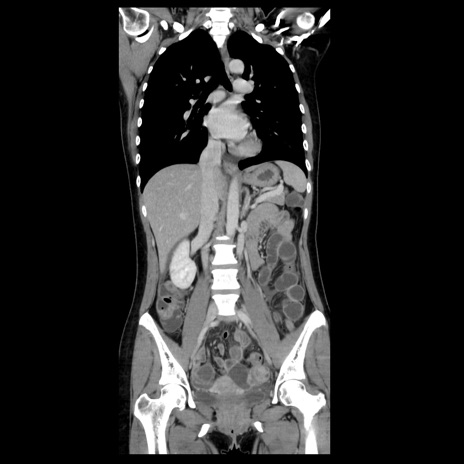

症例39(冠状断像)

【症例】40歳代女性

【主訴】上下腹部痛

【現病歴】2日目から下腹部痛あり。夜間は痛みで眠れなかった。昨日より上腹部痛と下痢が出現。臥位で痛みは軽快したため、休んでいた。本日になって臥位でも立位でも痛みが強くなってきたため救急要請。

【既往歴】子宮内膜症

【身体所見】部:平坦・軟、左上下腹部に圧痛あり、反跳痛あり。

【データ】WBC 21800、CRP 26.78

CT